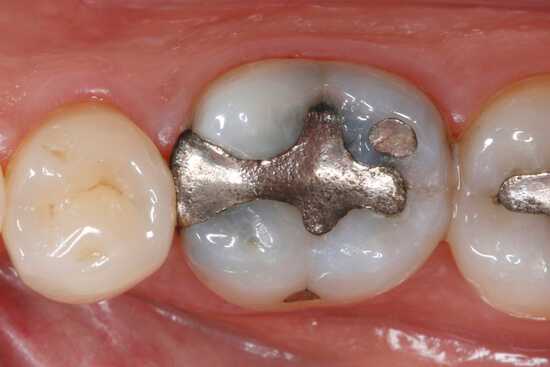

Пломба. Черные зубы могут быть результатом пломбирования. Некоторые виды композита содержат в своем составе вещества, которые окрашивают дентин и коронку. Современная стоматология не использует подобные материалы, но если зуб был запломбирован более 7-10 лет назад, подобные причины не исключают.

Вкладка металлическая. Для металла свойственно окисление, что может легко вызвать потемнение зубной эмали.

Установка амальгамной пломбы

Амальгама - сплав одного или нескольких металлов со ртутью. Содержание серебра в такой пломбе способствует дисколориту дентина.

Пломбы из амальгамы

Амальгамные пломбы уже не используются в современной стоматологии, но последствия такого восстановления зуба специалисты наблюдают и сегодня. В амальгаме содержится серебро. Со временем это вещество проникает в глубокие ткани дентина и окрашивает зуб в темно-серый цвет.

Амальгамные пломбы — амальгама может состоять из серебра, галлия и ртути. Серебро проникает в дентин и окрашивает его в темный цвет.